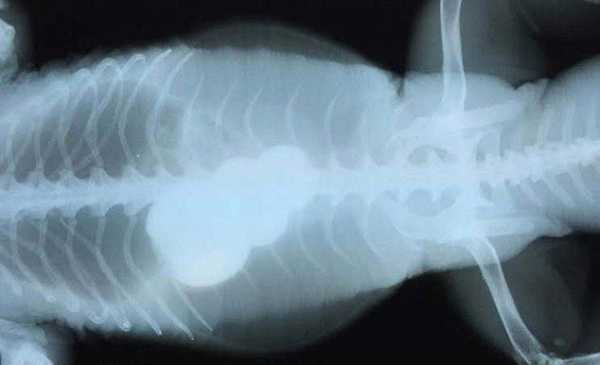

Однорічний кіт, який з'їв 30 гумок для волосся

А ось і вони, витягнуті з його живота